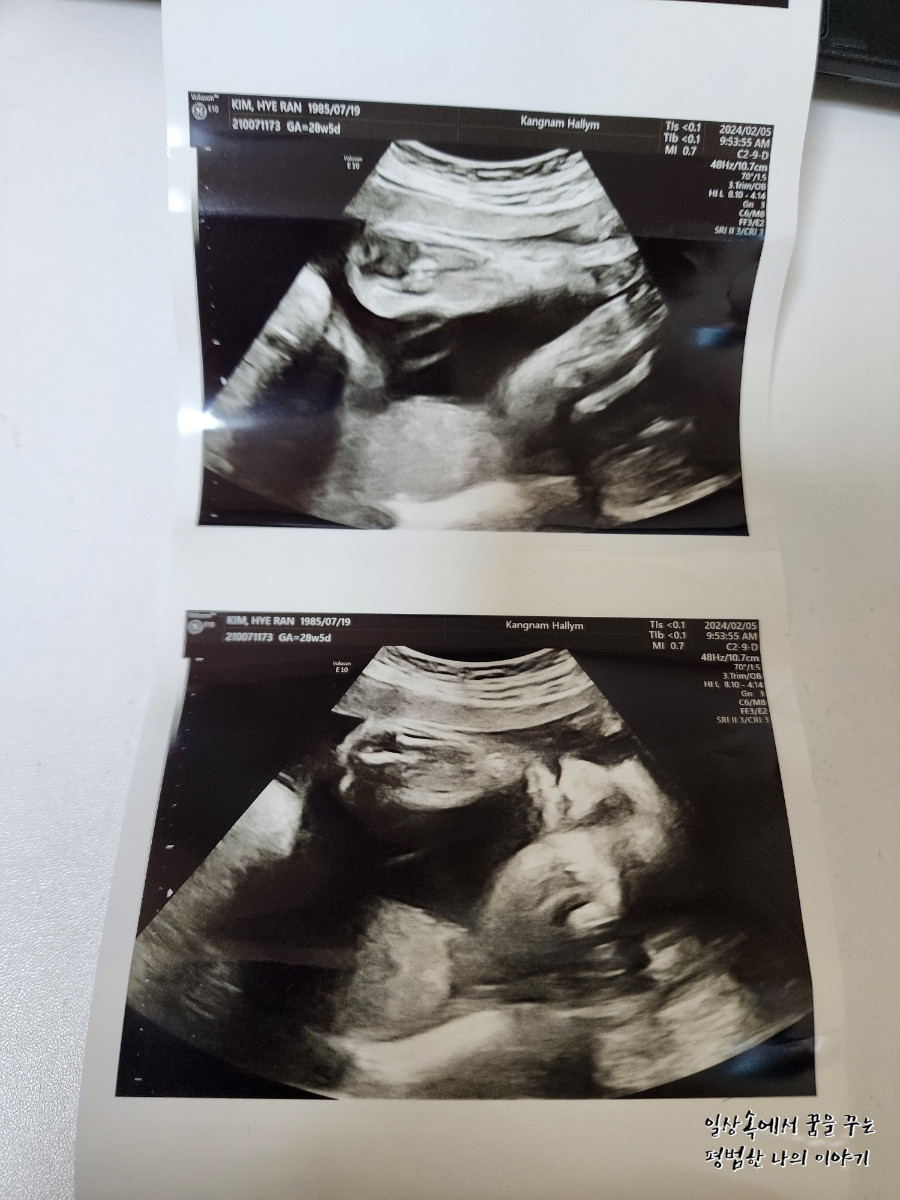

이번에 오랜만에 보는 초음파라 얼굴이라도 볼 수 있으려나 내심 기대하고 갔는데 얼굴을 아래쪽으로 향한 채로 뒤돌아 있어서 얼굴 보기가 쉽지 않았다. 그나마 막판에 두 손으로 얼굴을 살짝 가린 채 하품하고 있는 모습을 보여줬다. 남편 말로는 첫째보다 볼살이 더 많은 것 같다며 왠지 첫째보다 더 클 것 같다고... 무럭무럭 잘 자라줘서 고마워.